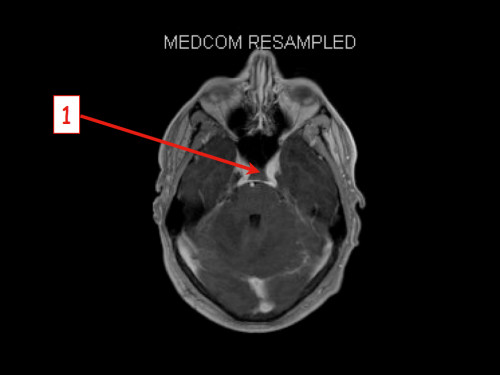

3. Schwindel und Kopfschmerzen, 3 Jahre nach Phäochromozytom-Resektion

Schwindel und Kopfschmerzen, 3 Jahre nach Phäochromozytom-Resektion

19-jähriger Mann. Er klagt seit mehreren Wochen über Schwindel und Kopfschmerzen. Im Alter von 16 Jahren sind er und sein Zwillingsbruder an einem Phäochromozytom operiert worden.